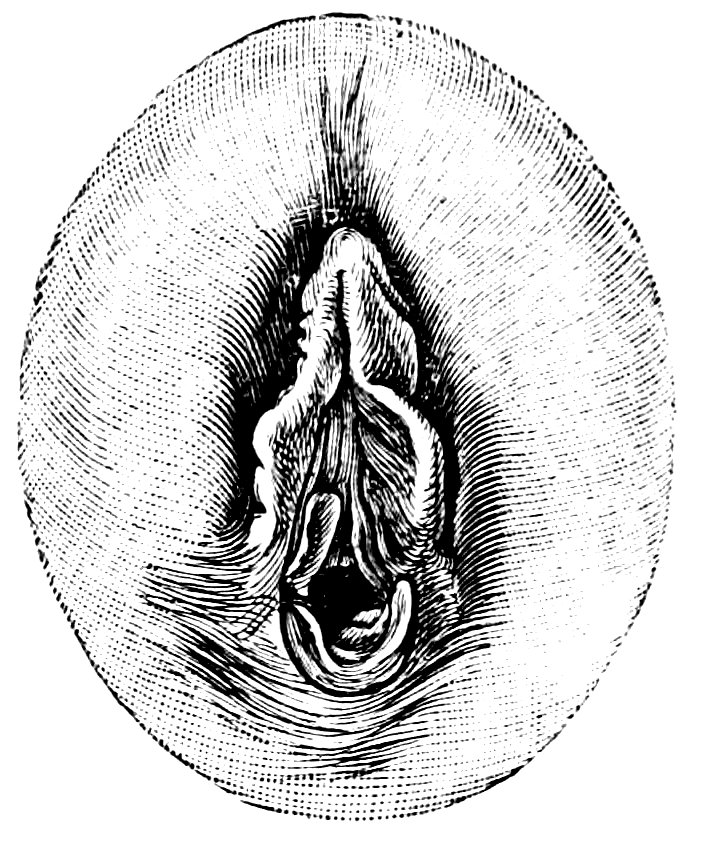

| 12. | Female external genital organs of a virgin | 54 |

| 13. | The external genital organs of a virgin | 55 |

| 18. | Annular Hymen | 64 |

| 19. | Annular Hymen | 64 |

| 20. | Semilunar Hymen | 65 |

| 21. | Annular Hymen with Congenital Symmetrical Indentations | 65 |

| 22. | Fimbriate Hymen | 65 |

| 23. | Deflorated Fimbriate Hymen | 65 |

| 24. | Septate Annular Hymen | 67 |

| 25. | Septate Semilunar Hymen | 67 |

| 26. | Extremely tough Annular Hymen with an obliquely disposed Septum | 67 |

| 27. | Septate Hymen with Apertures of unequal Size | 67 |

| 28. | Septate Hymen with Apertures of unequal Size | 68 |

| 29. | Hymen with rudimentary Septum | 68 |

| 30. | Hymen with posterior rudimentary Septum | 68 |

| 31. | Labiate Hymen with posterior rudimentary Septum | 68 |

| 32. | Hymen with anterior rudimentary Septum | 69 |

| 33. | Hymen with anterior rudimentary Septum projecting in a opiniform Manner | 69 |

| 34. | Hymen with anterior and posterior rudimentary Septa | 69 |

| 35. | Hymen with filiform Process projecting from the anterior Margin | 69 |

| 36. | Hymen in which there are two symmetrically disposed thinned Areas. The left of these is perforated | 69 |

| 37. | Very unusual form of Hymen | 70 |

| 38. | Semilunar Hymen with cicatrized Lacerations in its Border | 70 |

| 39. | Deflorated Semilunar Hymen with laterally disposed symmetrical Lacerations | 70 |

| 40. | Deflorated Annular Hymen with several cicatrized Lacerations | 70 |

| 41. | A. Septate Hymen in which defloration has been effected through one of the Apertures. U. Urethra. Cl. Clitoris. H. Cicatrized Margin. C. Septum. B. Lateral view of Septum | 70 |

| 42. | Deflorated Septate Hymen | 71 |

| x43. | Hymen with larger anterior and smaller posterior Apertures | 71 |

| 44. | Carunculæ Myrtiformes in a Primipara | 71 |

| 45. | Vaginal Inlet of a Multipara, without Carunculæ Myrtiformes. Slight Prolapse of Anterior and Posterior Vaginal Walls | 71 |